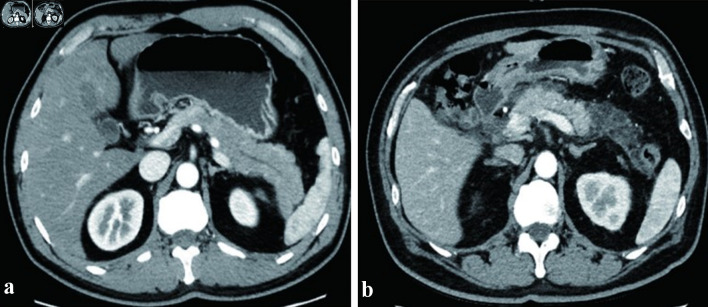

Results: The results indicated that among all 110 elderly SAP patients, the incidence rate of peripancreatic infection was 20.91%, with a mortality rate of 0.91%. MSCT perfusion imaging revealed that after peripancreatic infection in elderly SAP patients, there was a decrease in pancreatic density, local enlargement of the pancreas, blurring of the pancreatic margins, and associated ascites. Compression/narrowing/occlusion of the splenic vein was observed in 22 patients, compression/narrowing/occlusion of the superior mesenteric vein in 17 patients, thickening/thrombosis of the portal vein in 19 patients, and collateral circulation in 21 patients. Compared to elderly SAP patients without peripancreatic infection, those with the infection showed prolonged peak times, reduced peak heights, and decreased blood flow. ROC analysis indicated that the combination of the three parameters (peak time, peak height, and blood flow) had higher specificity and area under the curve (AUC) than single parameters, with no significant difference in sensitivity between the combination and single parameters.